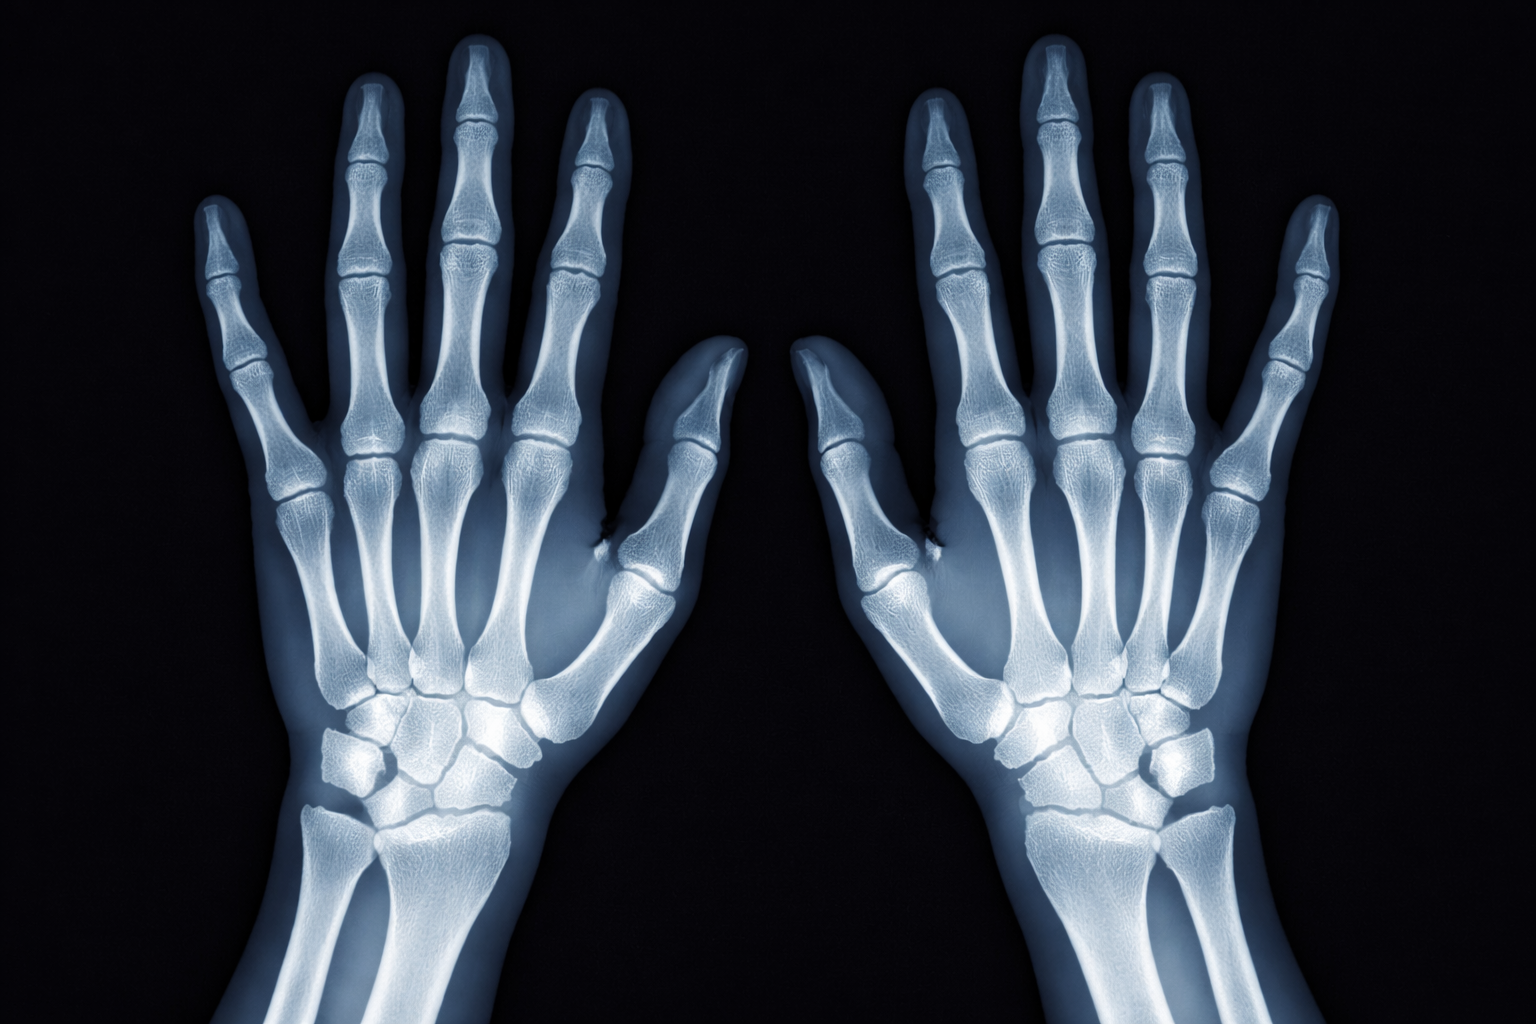

Данную патологию впервые описал немецкий врач П. Зудек в 1900 году, обнаружив на рентген-снимке пациента после сращения перелома некоторые изменения костной структуры и связал их с локальными вегетативными реакциями.

Причины возникновения наиболее часто связаны с травмами, переломами костей. Наиболее часто в практике врача встречается развитие данной патологии в процессе лечения перелома лучевой кости в типичном месте. Особенно, если данный вид перелома был со смещением и травматолог производил репозицию перелома. Повторные репозиции при данной травме в несколько раз увеличивают риск развития данного синдрома и значительно удлиняют сроки восстановления и нетрудоспособности. Так же длительная и неадекватная и неправильная иммобилизация гипсом поврежденных сегментов, отсутствие контроля за отёком мягких тканей, незнание сроков иммобилизации и фиксация конечности в нефизиологическом положении приводят к развитию данной патологии. Нарушается трофика и питание тканей в области перелома, местная тканевая гипоксия и реакции симпатической нервной системы приводят к изменению структуры кости, развитию пятнистого остеопороза, спаечного процесса в сухожильно-связочном аппарате и стойкой контрактуре смежного или повреждённого сустава.